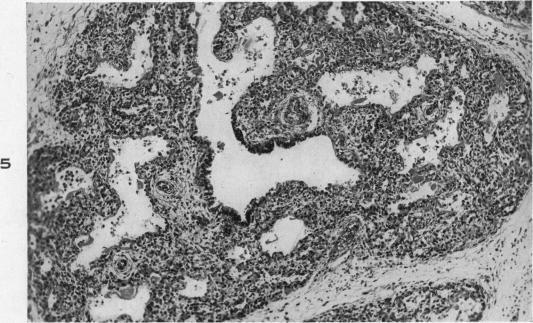

Congenital alveolar dysplasia of the lungs.

Am J Pathol. 1948 Jul;24(4):919-31.